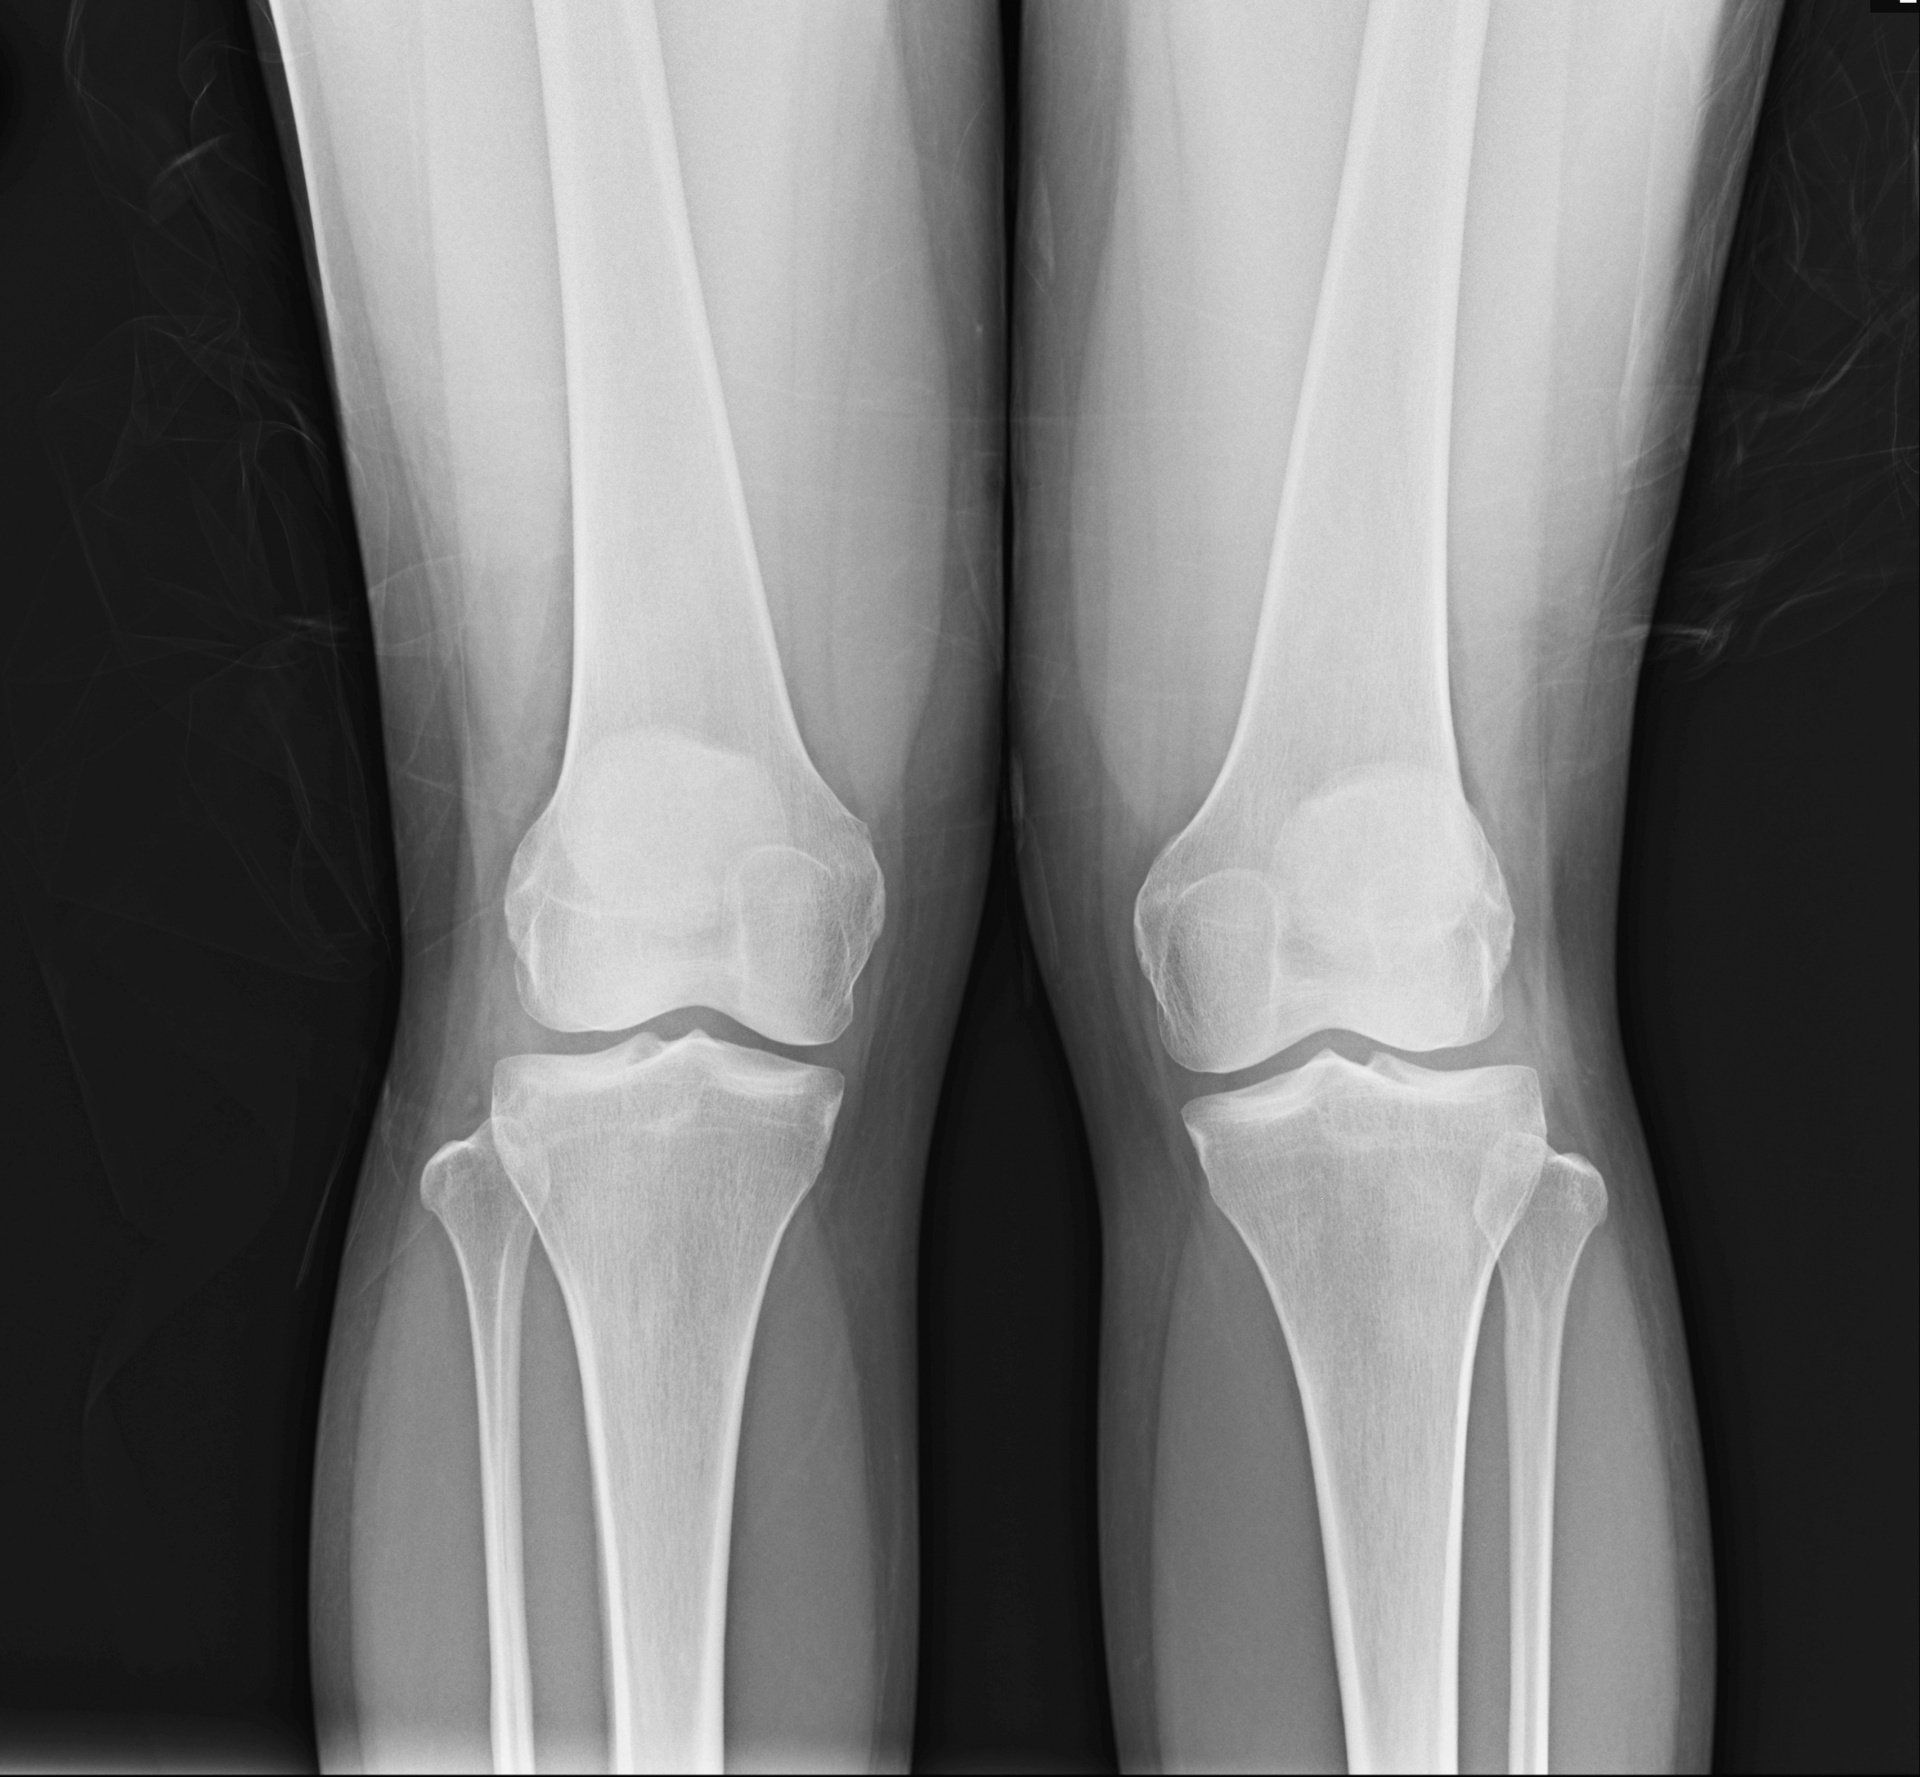

- Ακτινογραφίες:

- Φας και προφίλ

- Οι ακτινογραφίες λαμβάνονται για να επιβεβαιώσουν τη διάγνωση και πρέπει να είναι σε ορθία θέση, έτσι ώστε να ανιχνεύεται καλύτερα ο βαθμός στένωσης του μεσάρθριου διαστήματος που είναι ένα από τα βασικά χαρακτηριστικά της οστεοαρθρίτιδας